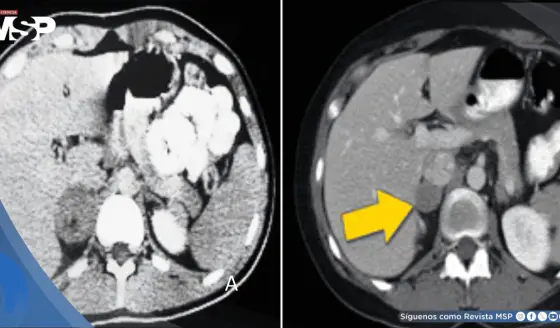

El análisis de 76 pacientes del Centro Médico Nacional de Occidente reveló datos epidemiológicos contundentes: el 70% presentaba obesidad, el 40% diabetes o prediabetes, y la mayoría cursaba con hipertensión arterial.

Estos pacientes no solo fueron diagnosticados en estadios más avanzados, sino que "en el seguimiento vimos que llegaban y respondían peor al tratamiento". La obesidad y el diámetro de la cintura abdominal emergieron como los factores pronósticos más significativos para evolución desfavorable.